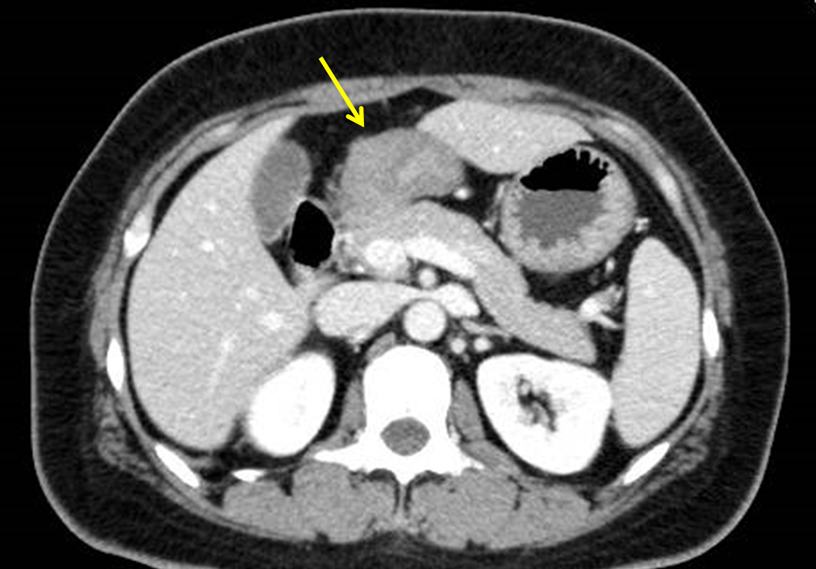

胸腹部造影CT所見:十二指腸球部に全周性の壁肥厚を認めた(Fig. 2).リンパ節転移,遠隔転移を疑う所見は認めなかった.

Enhanced CT examination reveals wall thickening of the duodenal bulb (yellow arrow).